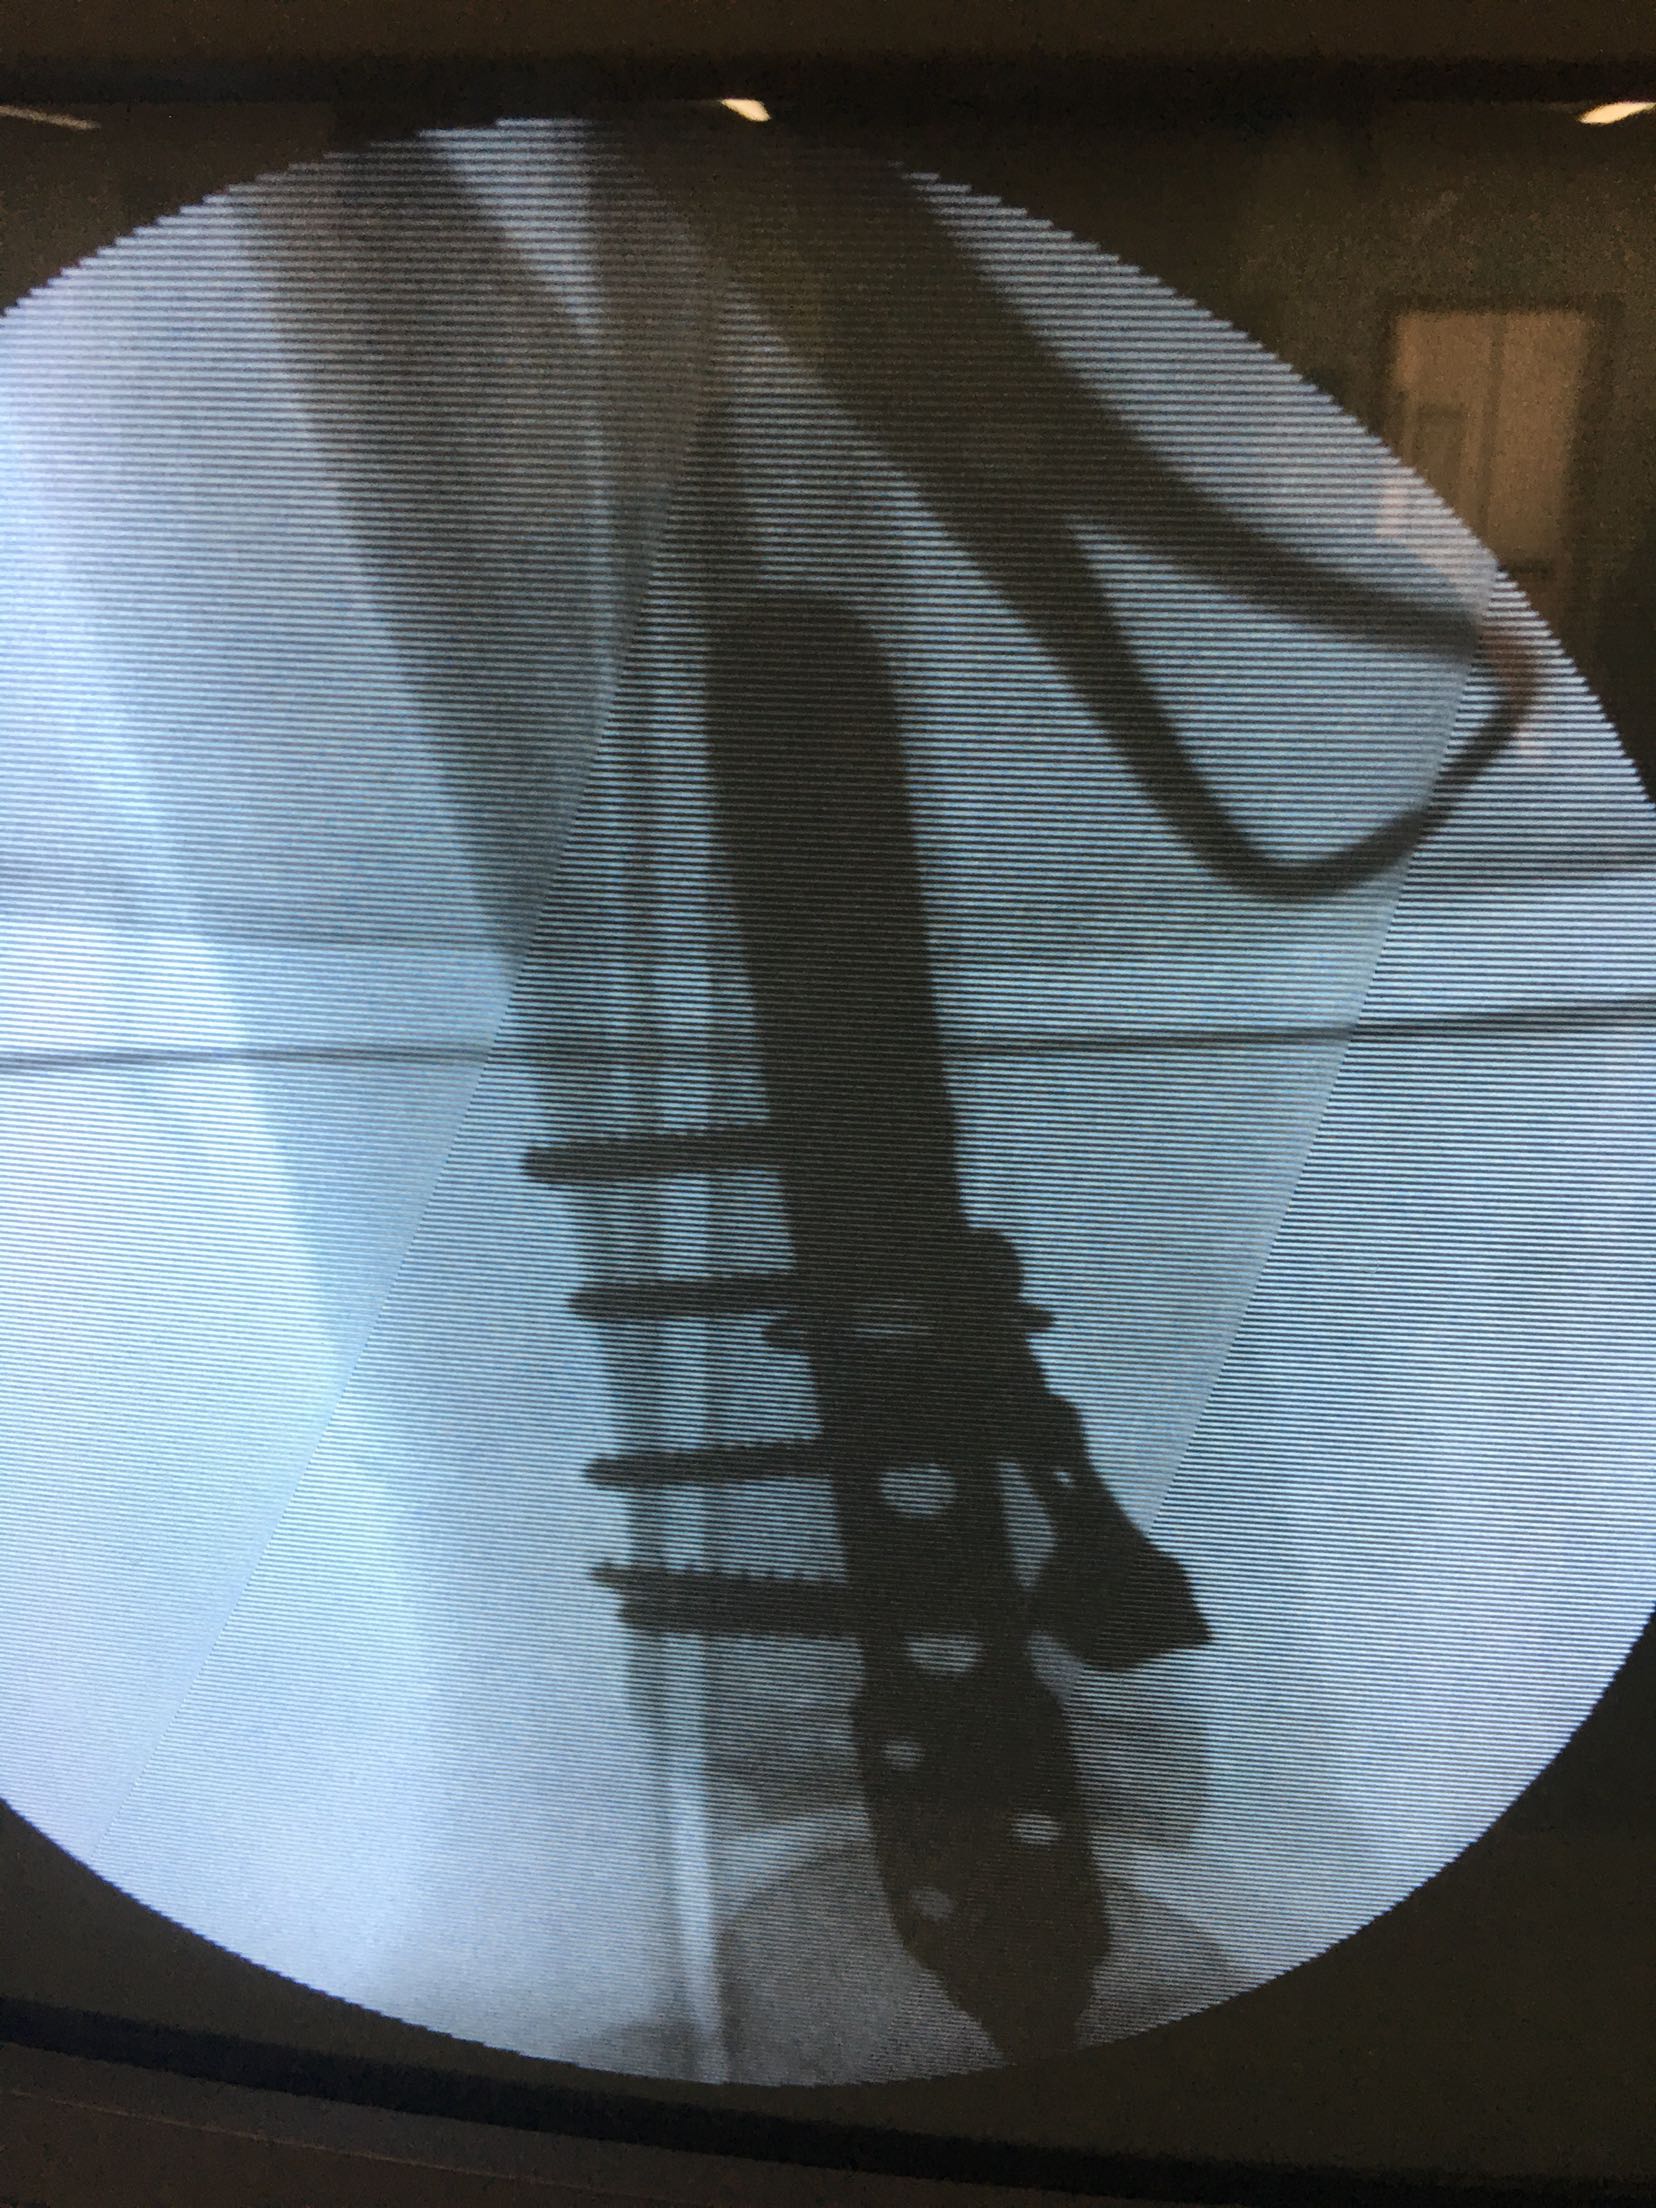

急诊在局麻行左跟骨结节骨牵引术一周。今日在腰麻下行切复内固定术,术后抗炎,消肿止痛等处理,石膏托制动3-4周。